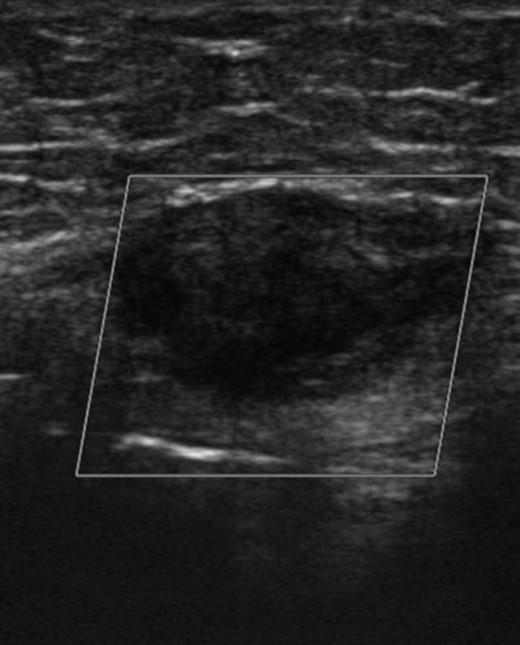

A 32-year-old lady was referred to our clinic with complaints of a painful lower abdominal lump. It had been present for 4 months and had become more symptomatic over time. She had a past medical history of hyperthyroidism but nothing else of note. Abdominal examination revealed a 2-cm infra-umbilical palpable lump within the left rectus muscle which was mildly tender and did not have a cough impulse. An ultrasound scan showed a hard 2 × 3 cm lesion in her left rectus and no evidence of a hernia (Fig. 1). To characterize the lesion further, an magnetic resonance imaging (MRI) scan was organized and it revealed a benign lesion consistent with an intramuscular lipoma (Fig. 2). She was taken to the theatre for excision of the lump. Intra-operatively she was found to have an inflammatory mass and therefore a wide excision was carried out. The patient was discharged with no complications. Histological examination revealed endometriosis of the abdominal wall. She has been followed for 6 months with no signs of a recurrence.

Ultrasound scan showing a hard 2 x 3cm lesion in her left rectus.